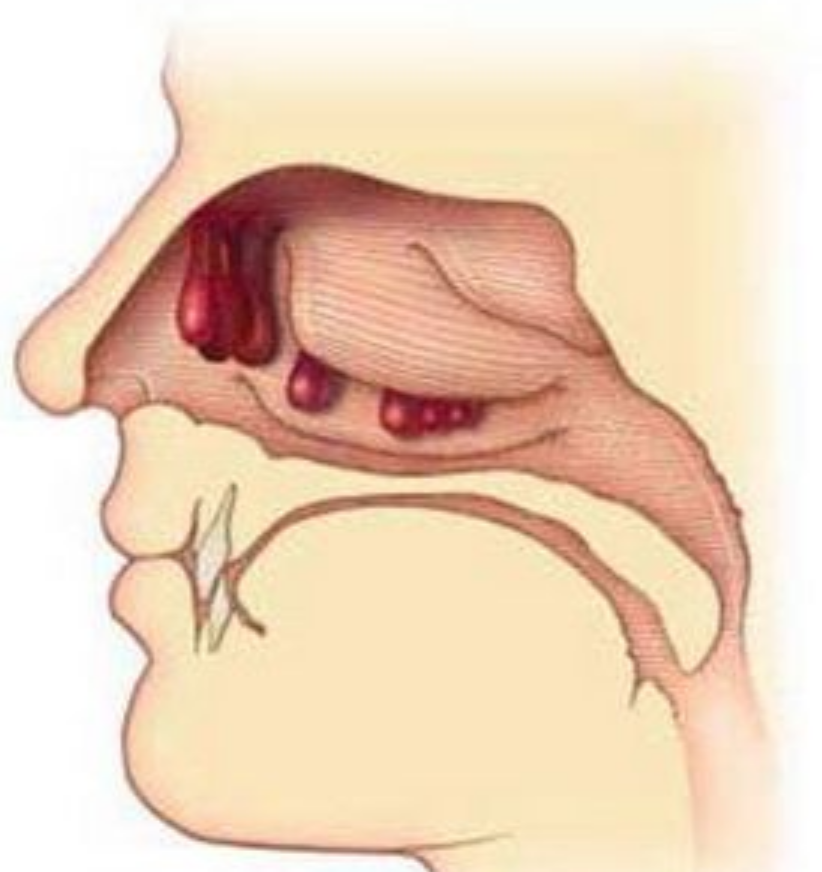

鼻息肉